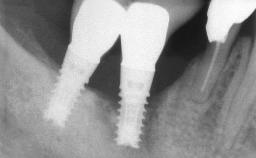

| # of Implants | 4 |

| Attachment | One-Piece |